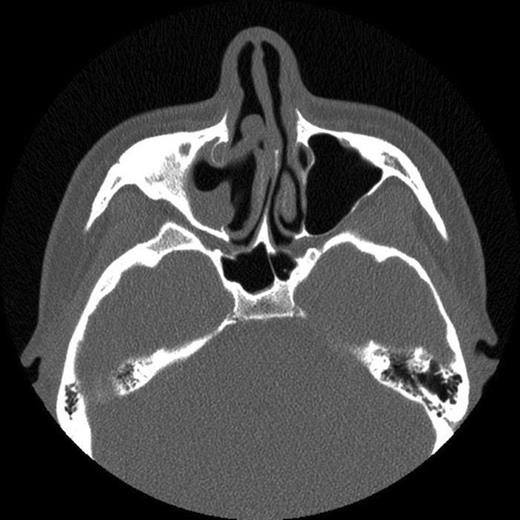

The patient then attended our clinic. Clinical examination and subsequent naso-endoscopy showed evidence of a right sided nasal obstruction with polypoidal mass within the nasal cavity. The patient underwent CT scan sinuses, which showed a well demarcated air defect in the extensively thickened sinus mucosa with large polypoidal mass. Evidence of entry of the cue was seen as a defect in the anterolateral wall of the right maxillary sinus and absent upper medial wall. No FB was seen.

CT scan showing fracture of the anterolateral wall of the right maxillary sinus and absent upper medial wall